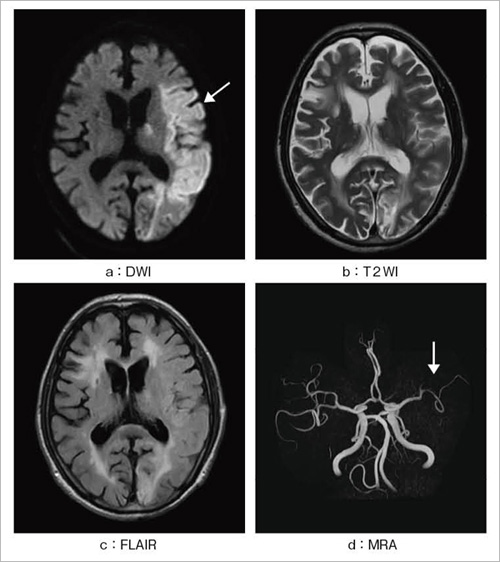

ECHELON VegaによるMRIファーストの診断で石川県の脳神経疾患治療の最前線を担う-医療法人社団浅ノ川 金沢脳神経外科病院-inNavi Suite,![Figure 2. [MRI findings in three persons with CTX]. - GeneReviews® - NCBI Bookshelf Figure 2. [MRI findings in three persons with CTX]. - GeneReviews® - NCBI Bookshelf](https://www.ncbi.nlm.nih.gov/books/NBK1409/bin/ctx-Image002.jpg) Figure 2. [MRI findings in three persons with CTX]. - GeneReviews® - NCBI Bookshelf

Figure 2. [MRI findings in three persons with CTX]. - GeneReviews® - NCBI Bookshelf